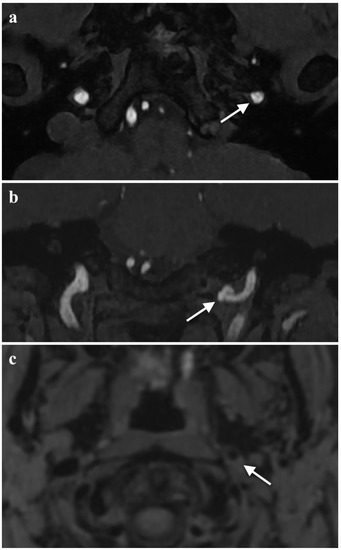

2.2. Diagnosis